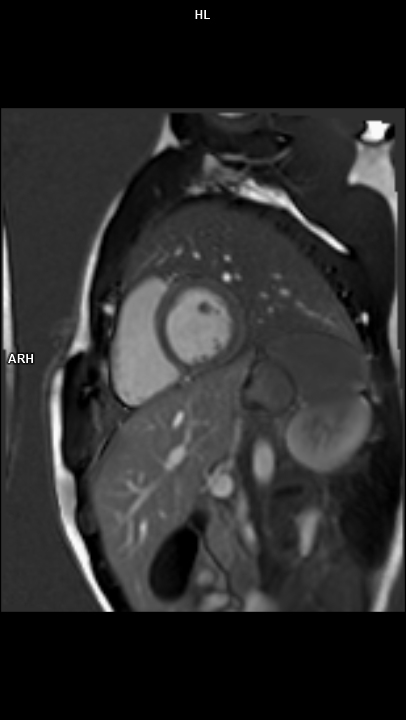

• 3 TESLA MR ÇEKİM GÖRÜNTÜLERİ

3 Tesla MR Çekim Görüntüleri

• 3 Tesla MR Çekim Görüntüleri